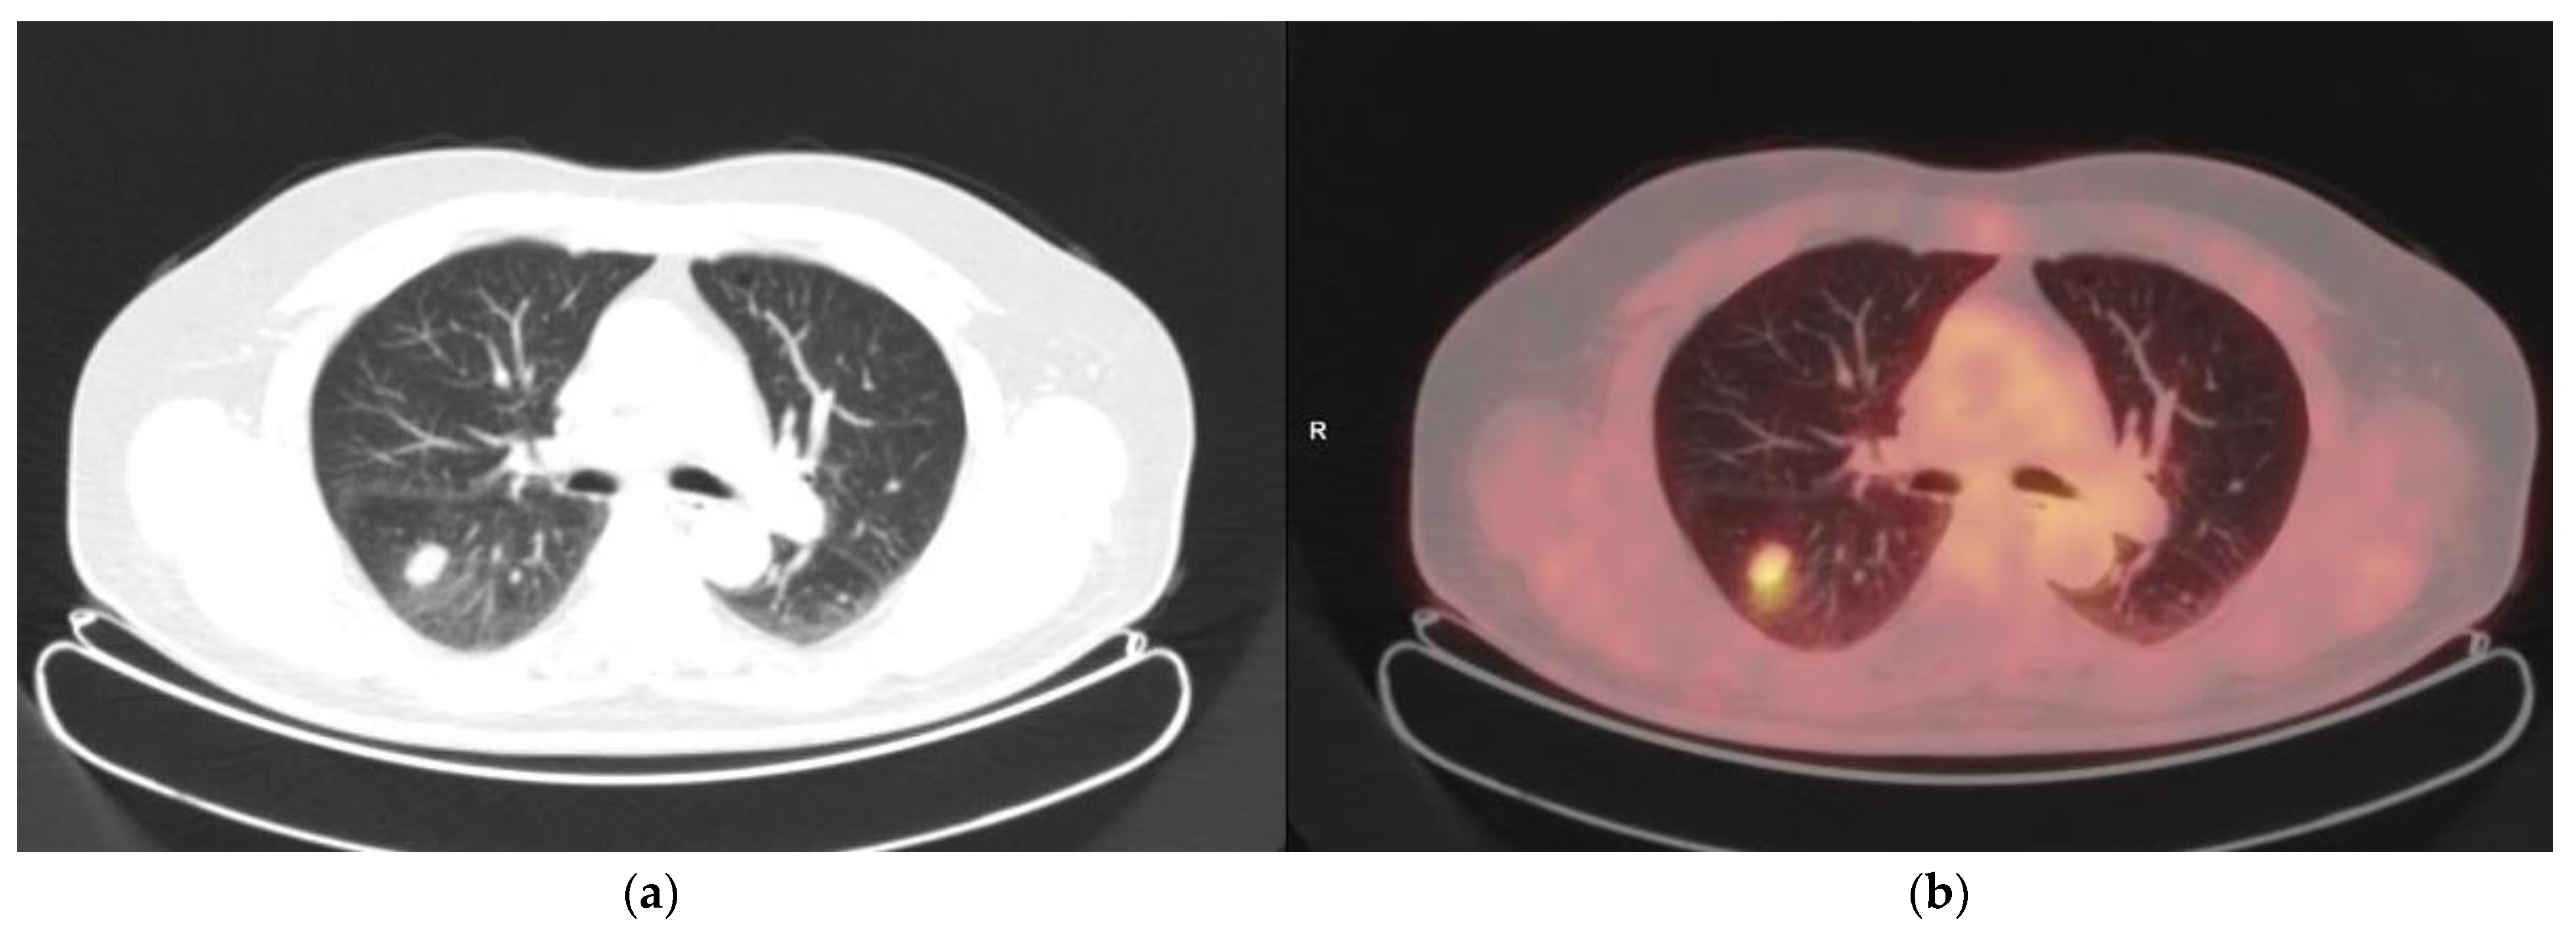

3.5. DA of FDG PET/CT for Cutaneous Lesions

3.6. Per Site Analysis of FDG PET/CT DA for Extra-Cutaneous Lesions

| Lungs | 7 | 0 | 67 | 1 | 87% | 100% | 100% | 98% | 99% |